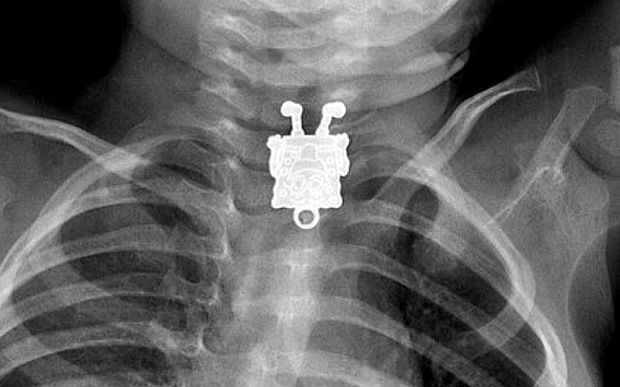

Il medico che ha visitato il piccolo Ghofran Ageely, è rimasto molto sorpreso quando, credendo che il bambino avesse ingerito qualcosa di più piccolo, come una spilla, invece ha nitidamente visto, attraverso i raggi x, che c’era uno SpongeBob nello stomaco del bimbo.

Una sagoma così non poteva passare certo inosservata. Grazie alle radiografie effettuate su un bimbo di soli 16 mesi, è stato possibile capire che il piccolo aveva ingoiato un pupazzo di SpongeBob. E’ successo in Arabia Saudita.